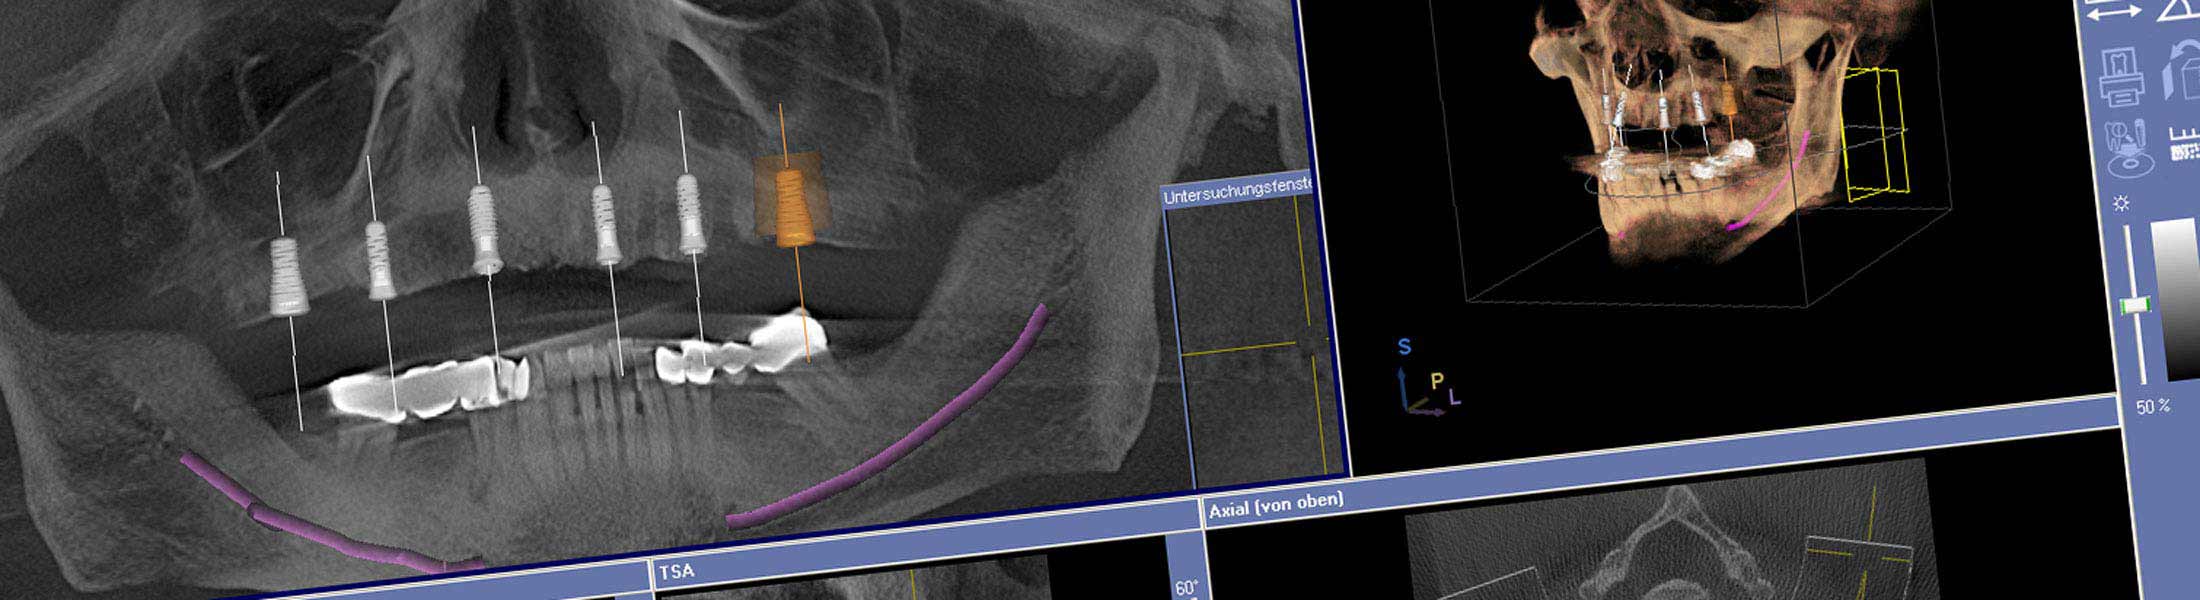

Die Analyse der Daten der digitalen Implantatplanung liefert präzise Informationen über die bestmögliche Zahnstellung. Mit einer speziellen Planungssoftware wird das passende Implantatdesign gewählt und die optimale Implantatposition festgelegt. Die computerunterstüzte Planung und Implantatinsertion mit Hilfe einer Bohrschablone ermöglicht eine Positionierung des Implantates, die exakt auf Grundlage der prothetischen Planung erfolgt.

Beim Backward-Planning wird auf Grundlage der angestrebten prothetischen Versorgung rückwärts geplant. Die Implantate werden genau da inseriert, wo die Planung des Zahnersatzes sie zur optimalen Befestigung und für eine ansprechende Ästhetik benötigt.